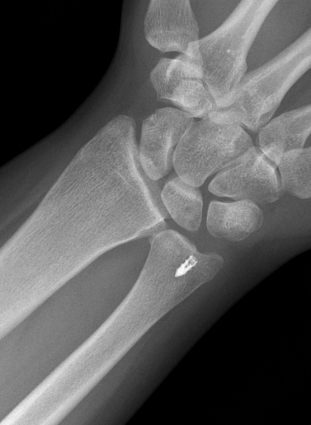

Isolated ulna styloid fractures with DRUJ instability

Classification ulna styloid process fractures

| Type 1: Tip fracture | Type 2: Base fracture |

|---|---|

|

Stable DRUJ

DRUJ potentially unstable |

Ulna styloid process fracture and acute DRUJ instability

Ulna styloid fracture with TFCC injury